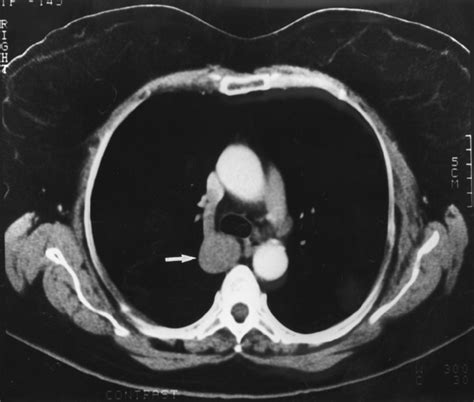

While standard chest X-rays are usually sufficient for diagnosis, computed tomography (CT) provides a definitive view. On a CT scan, the Vena Azygos Lobe is clearly demonstrated as an isolated pleural-lined segment of lung tissue separated from the rest of the right upper lobe by the azygos fissure.